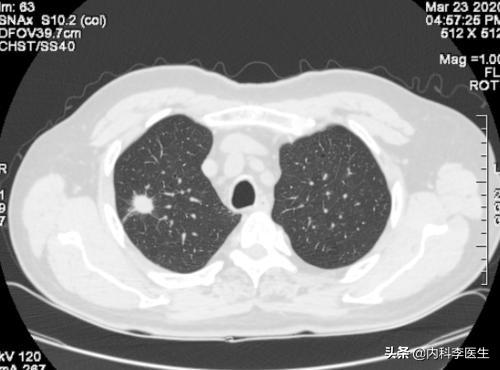

健康診断への意識が高まるにつれ、肺結節が発見される人が増えている。肺結節とは画像診断の用語で、肺結節の画像上の定義は、肺実質に完全に囲まれた、境界明瞭な小さな病変(直径≤30mm).結節の形態は、固結または亜固結に分類される。亜固結はさらに、純粋なすりガラス結節と部分的な固結に分類される。直径30mmを超える病変は結節ではなく腫瘤であり、悪性の可能性が高い。

肺結節とは、胸部CTを撮影したときに映し出される肺の影を表す画像用語で、肺の中の多くの病気が肺結節を呈することがあります。

肺結節は、フィルムやCTで肺に結節性病変が検出される画像概念である。

肺結節:肺の組織に現れる病変である。直径30mm以下の円形または不規則な病変で、正常な肺組織に囲まれていることが多い。医用画像では「肺の高密度陰影」と表現される。肺小結節は単結節または多結節で、境界が明瞭なものと不明瞭なものがある。

Qualitative:肺結節は、本人や家族では発見できない、あるいは発見しにくい異常で、病院で健康診断などの検査を受けたり、肺のCT、X線、MRiなどの検査をして初めて発見されることが多い身体的な異常です。